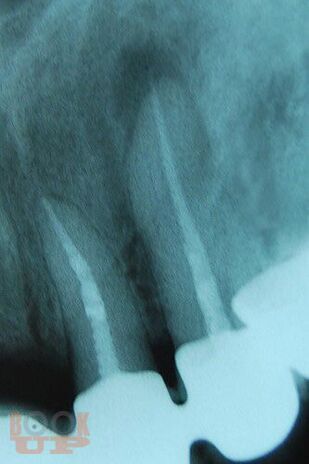

В учебном пособии на современном уровне освещены показания, противопоказания, техника выполнения зубосохраняющих операций при лечении хронических периодонтитов, а также методы предоперационной подготовки больных к хирургическому вмешательству и их послеоперационному ведению.